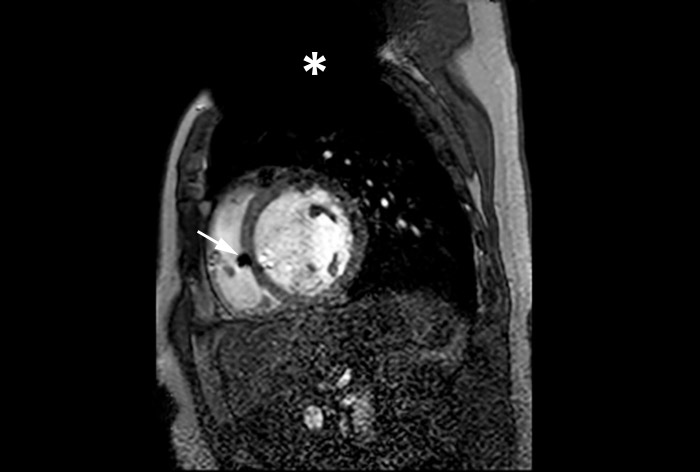

A patient with an MR Conditional ICD and suspected myocarditis presented for MRI. This short axis view of the heart is created with an SSFP (steady state free precession) sequence on a Philips Achieva 1.5T system. The cardiac MRI exam reveals normal dimensions and regular function of the right and left ventricle. Note the ICD lead in the right ventricle (arrow) and the signal void in the left pectoral region, indicating the ICD-IPG (asterisk). Courtesy of Dr. Sommer.